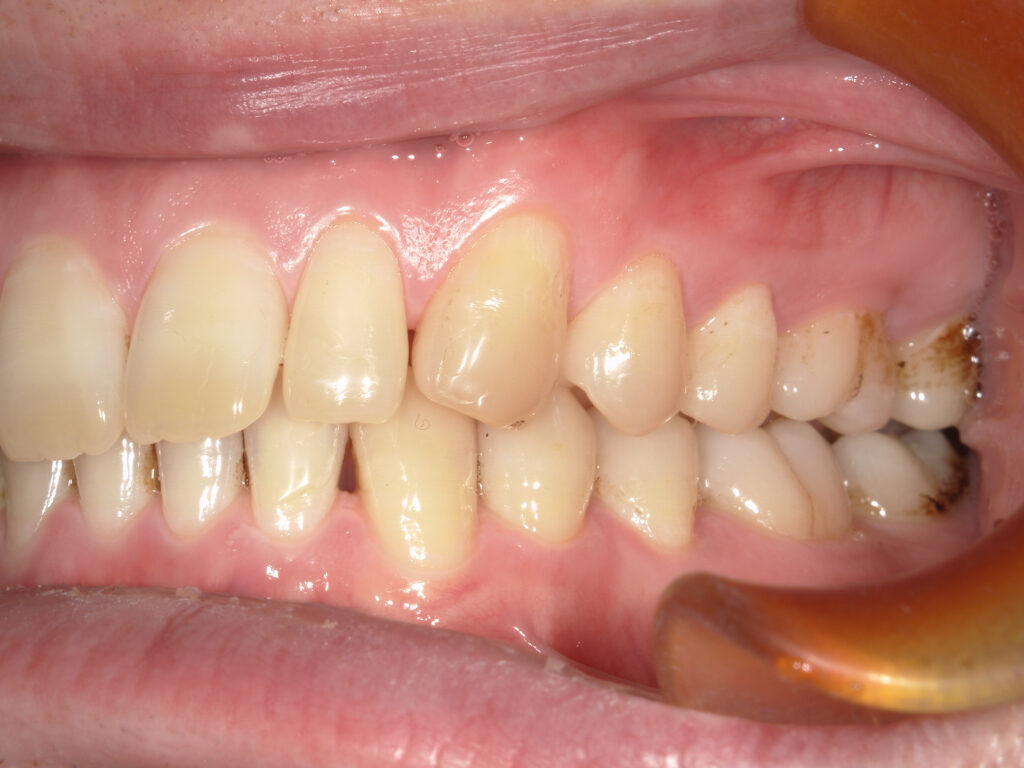

右側

治療前

治療後